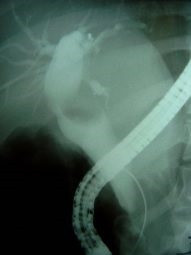

Cálculo gigante y divertículo duodenal ERCP

Envíado por Dr. Carlos Miguel Zavaleta Consuegra